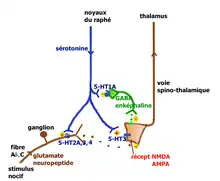

- Action au niveau de la moelle spinale : le premier relais de la transmission des informations nociceptives se trouve dans la corne dorsale de la moelle spinale. Le premier neurone des fibres Aδ ou C libère dans l'espace synaptique de ce relais des neurotransmetteurs excitateurs (glutamate, aspartate) et des neuropeptides (substance P, neurokinine A, CGRP, somatostatine, CCK et VIP). Le deuxième neurone qui croise la ligne médiane et monte vers le deuxième relais situé dans le thalamus, capte ces médiateurs ainsi que de nombreux médiateurs d'origines diverses : des peptides opioïdes (enképhaline, bêta-endorphine, dynorphine) émis par des interneurones inhibiteurs, eux-mêmes stimulés par les neurones de la voie descendante du raphé magnus ; la sérotonine émise par les neurones sérotoninergiques qui descendent des noyaux du raphé magnus.

Les neurones du raphé magnus, à l'origine de la majorité des projections sérotoninergiques, ont un rôle qui peut être pronociceptif ou antinociceptif, suivant le contexte physiologique et pharmacologique (Millan[30] 2001). L'explication tient à la présence en des lieux différents de récepteurs sérotoninergiques différents pouvant activer ou ralentir l'activité neuronale. Millan propose les deux voies illustrées ci-contre.

Lors de stimulations nociceptives intenses, la voie rétroactive inhibitrice entraîne la suppression des messages nocicepteurs au niveau de la moelle. On peut observer chez le rat que la stimulation électrique du raphé provoque la libération de la sérotonine au niveau médullaire avec inhibition des fibres C, stimulation des interneurones GABAergiques et enképhalinergiques bloquant complètement la transmission du message nocicepteur au niveau du deuxième neurone de la voie spinothalamique. La voie facilitatrice descendante serait principalement mise en jeu par la stimulation soutenue à la périphérie des fibres afférentes primaires se projetant dans la corne dorsale sur des cellules exprimant le récepteur NK1 de la substance P. Ces cellules activent par une voie indirecte les noyaux du raphé magnus[31]. La facilitation implique la présence des récepteurs 5-HT3 et 5-HT2A.